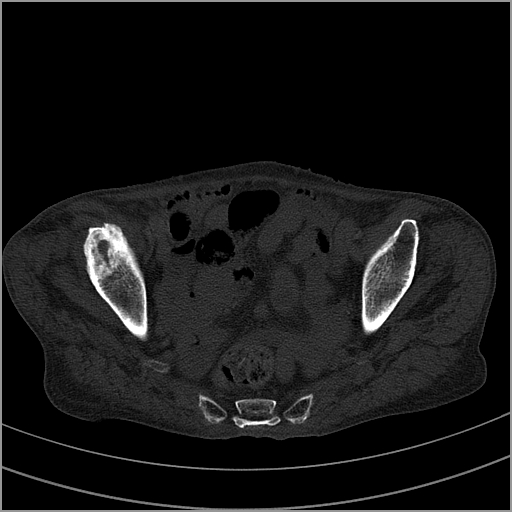

以下是引用老爱克斯新网客在2009-2-3 19:42:00的发言:[br]右侧髋臼及右侧股骨头可见明显骨质破坏,以溶骨性破坏为主,无明显硬化,髋关节间隙变窄,周围软组织明显肿胀,密度不均,脂肪间隙消失。[br] 诊断:右侧髋关节感染性病变,右侧髋关节结核的可能大。[br] 鉴别诊断:1.股骨头缺血坏死,单纯股骨头缺血坏死病例不会累积髋臼骨破坏。2。退行性关节炎,以骨质增生为主,伴有关节面硬化,骨质破坏呈多发小囊状破坏为主,其周围可见硬化环。3.股骨头缺血坏死晚期(第四期)骨质破坏可伴髋关节退行性变,可有骨质增生,但此时骨破坏以股骨头破坏为主,不应该伴有髋臼骨质破坏,因为股骨头的骨破坏是因血运中断,而没有髋臼的血运中断,又没有细菌的感染,怎么能造成髋臼的骨破坏呢。